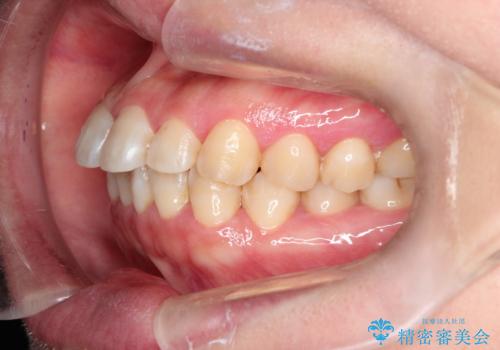

【インビザライン】前歯のすきまを閉じたい

- 前歯の隙間を主訴に来院されました。

インビザライン にて治療を行い、歯並びを改善することができました。